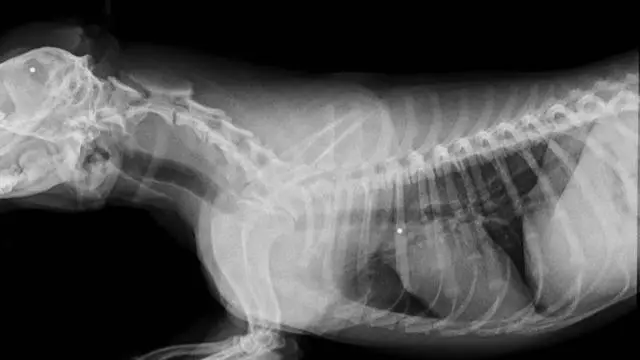

Röntgenaufnahme des angeschossenen Hundes. Im Kopf und in den Rippen wurden Schrotkugeln entdeckt / Redaktion DM

Der Vorfall ereignete sich Mitte Juli vergangenen Jahres im Inseldorf Consell. Dort fand die Halterin einen ihrer Hunde verletzt am Borden. Wie tierärztliche Untersuchungen ergaben, hatte er zwei Schrotkugeln im Kopf und in den Rippen. Ihr andere Hund blieb seitdem spurlos verschwunden. Die Frau vermutet, dass ihr Nachbar das Tier getötet und die Leiche versteckt habe. Unmittelbar zuvor hatte es wohl Streit zwischen der Hundehalterin und dem mutmaßlichen Schützen gegeben. Dieser hatte sich beschwert, weil die Hunde auf sein Grundstück gelaufen und seine Hühner gejagt hatten. Dabei soll er gedroht haben, die Tiere zu töten, falls sie erneut sein Grundstück betreten würden.